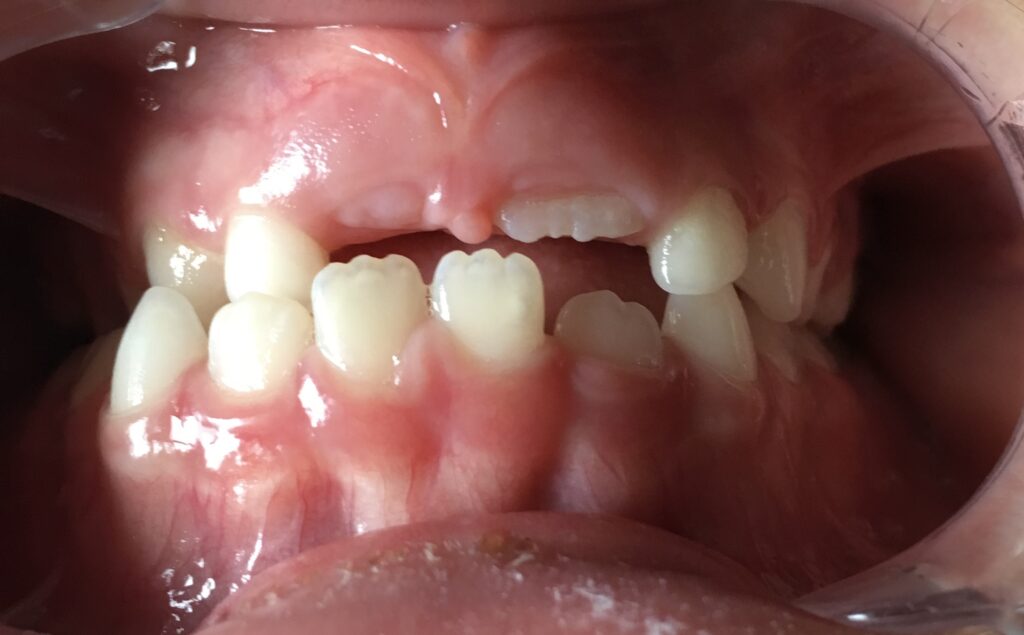

Dès la visite des 3 ans, il est possible de détecter certaines anomalies dentaires chez l’enfant, comme une béance ou un articulé croisé.

Une prise en charge précoce et non invasive permet de repérer d’éventuelles habitudes néfastes :

• respiration buccale,

• succion prolongée (tétine, pouce, biberon).